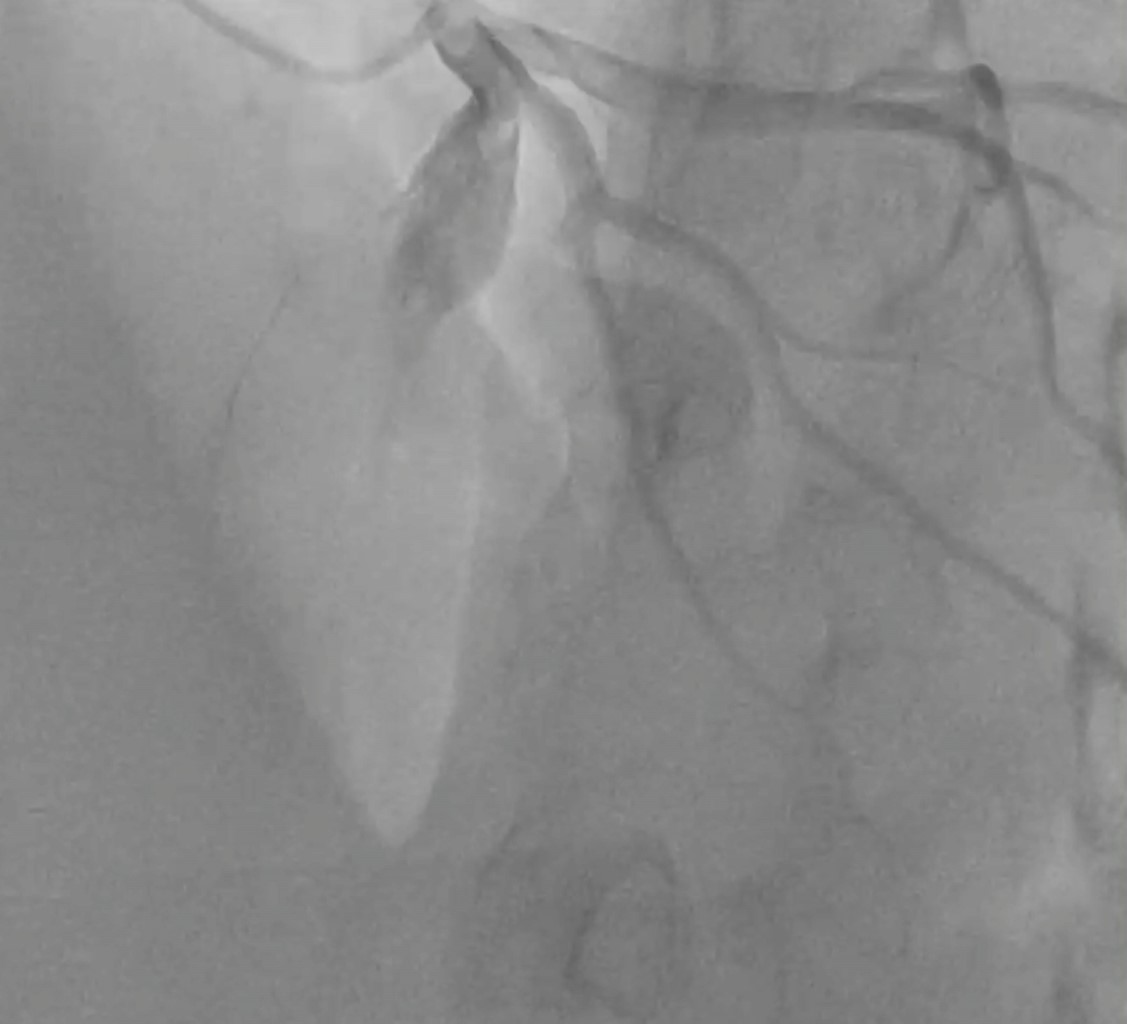

Aneurisma coronario: hallazgo incidental

Guzmán-Salgado JA, Ramírez J, Meza-Carmona J, Hernández-Rendón E, Tarelo-Saucedo JM, Ortega-Romo EE

El aneurisma de la arteria coronaria es una entidad rara en la población general. Presentamos el caso de un paciente masculino de 51 años con angina inestable, en quien se identificó un aneurisma de la arteria coronaria descendente anterior durante la intervención coronaria percutánea. El tratamiento quirúrgico consistió en ligadura, resección y revascularización coronaria, logrando una recuperación satisfactoria y siendo dado de alta cinco días después. La cirugía aneurismática es fundamental en el tratamiento de aneurismas verdaderos, especialmente en pacientes sintomáticos, como medida preventiva y óptima.

Figura 2